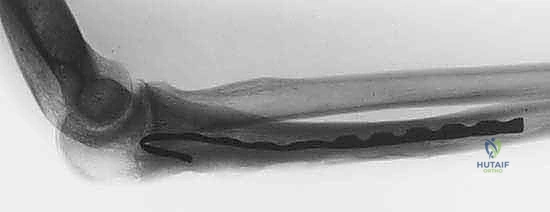

Example: Plain radiograph demonstrating an expansile, lytic lesion of the proximal humerus, consistent with an aneurysmal bone cyst, requiring careful assessment of cortical thinning.

Examples: Advanced imaging of a recurrent low-grade chondrosarcoma of the distal radius, noting precise anatomical location, cortical integrity, and intramedullary extension.